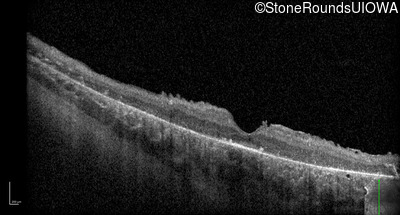

Optical Coherence Tomography - Right - 5/180 sc

Exemplar / OCT Stack

OCT Stack